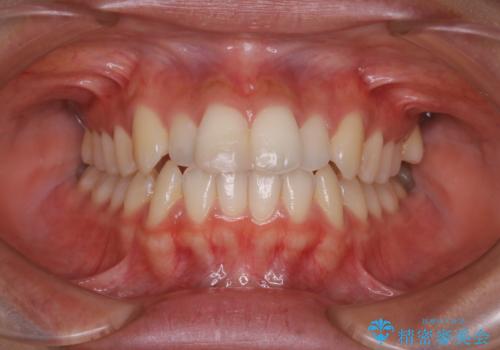

- 前歯の傾きと、ガタガタが気になるとのことで来院されました。

アスリートの方でしたので、競技に支障が少ないインビザラインで治療することとなりました。

前歯の傾きや高さをシミュレーションで患者様と確認しながら、歯並びを仕上げていきました。

遠方での合宿などで長期に来院できない場合も、インビザラインなら治療が可能となります。